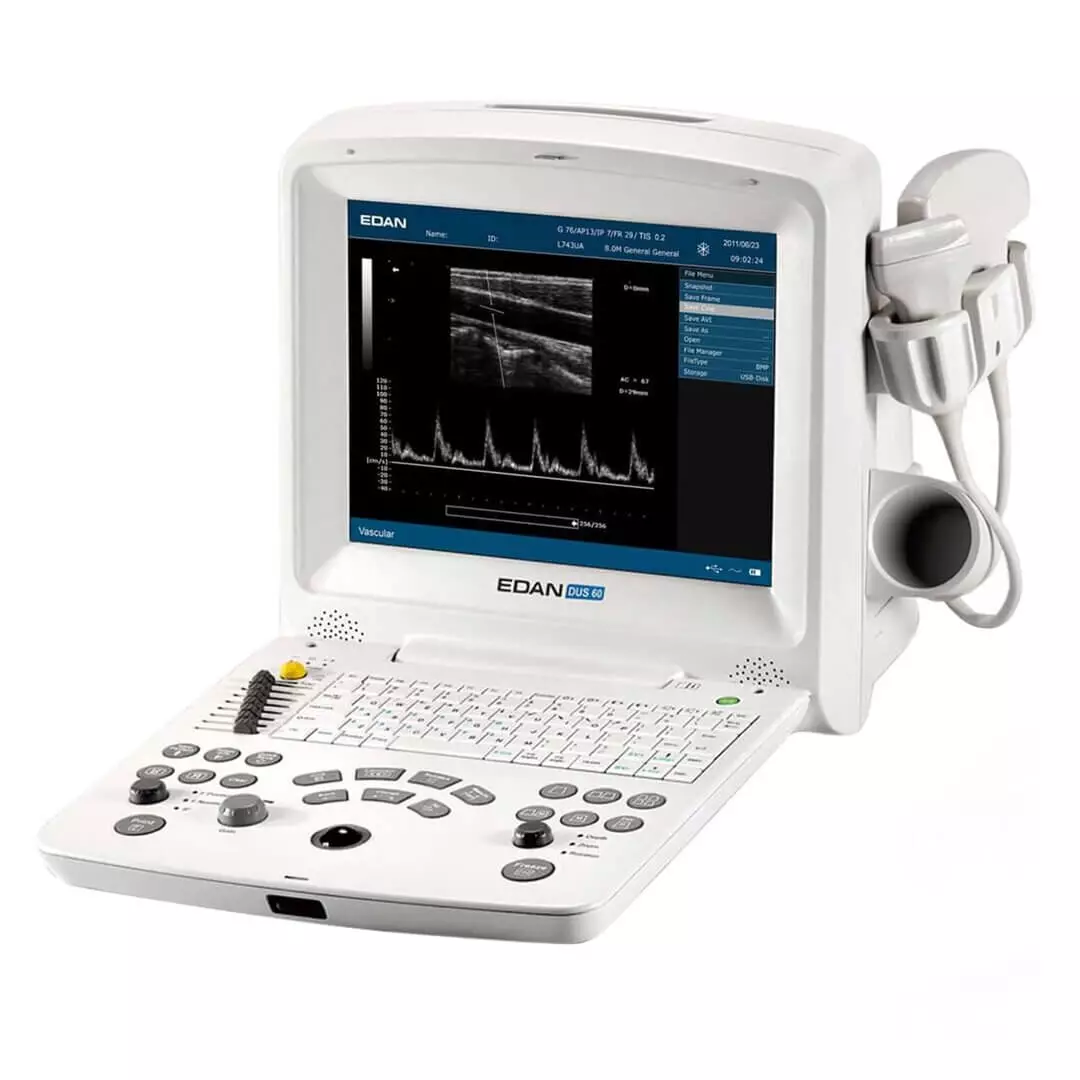

- Affichage en boucle des images : 256 images

- Avec imagerie harmonique tissulaire (Tissue Harmonic Imaging) et imagerie Doppler spectrale

- Sonde linéaire L743-2

- Applications : exposition de petites structures

- Fréquences : 6,5 MHz ; 7,5 MHz ; 8,5 MHz ; H9,0 MHz ; H9,4 MHz

| Domaine d’application | abdomen, vasculaire, thorax, petits organes, musculosquelettique |

| Imagerie | formation multi-faisceaux, PW Auto-Trace, Tissue Harmonic Imaging (THI, Compensation de gain temporel à 8 segments (TGC) |

| Modes d’affichage | mode B, mode M, doppler spectral, doppler PW |